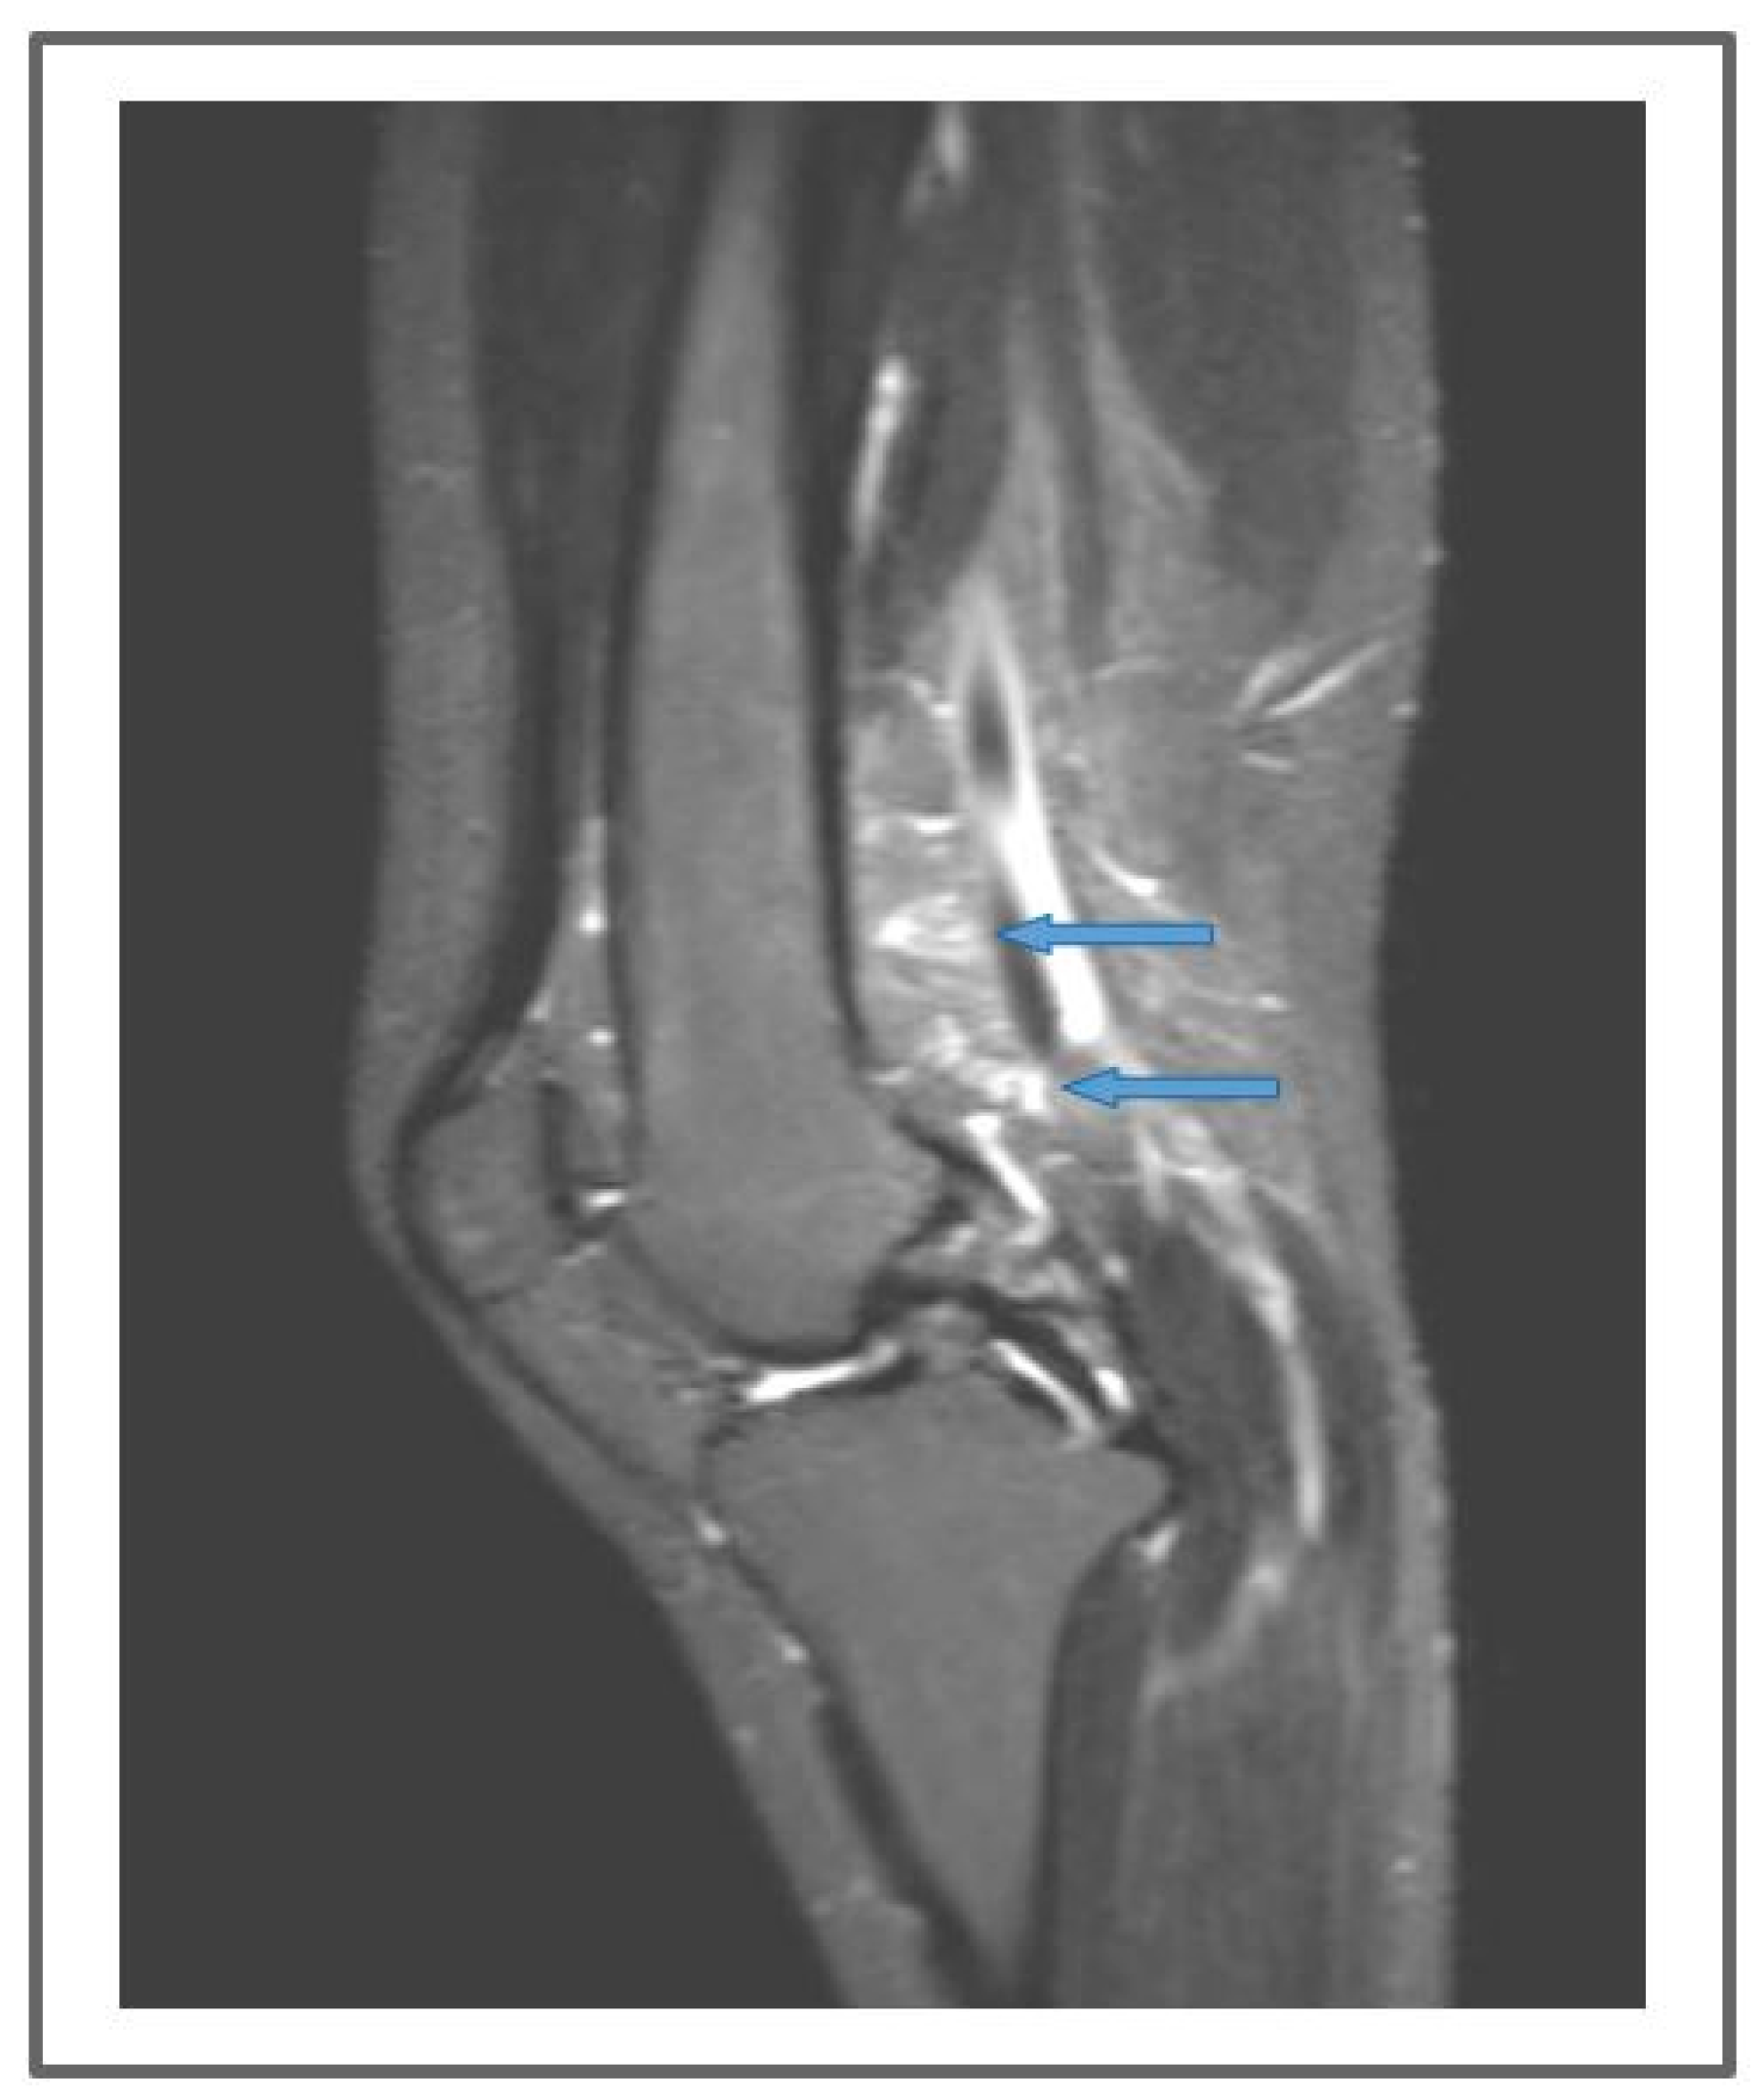

Figure 7.

Patient 3: Follow-up MR lymphography showing lymph nodes transplanted in the popliteal fossa (blue arrows) and coronal reconstruction of a 3D short-time inversion recovery (STIR) with repetition time 3000 ms, echo time 254 ms, inversion time 160 m, field of view 460 × 504 mm, matrix 315 × 384, slice thickness 1 mm.